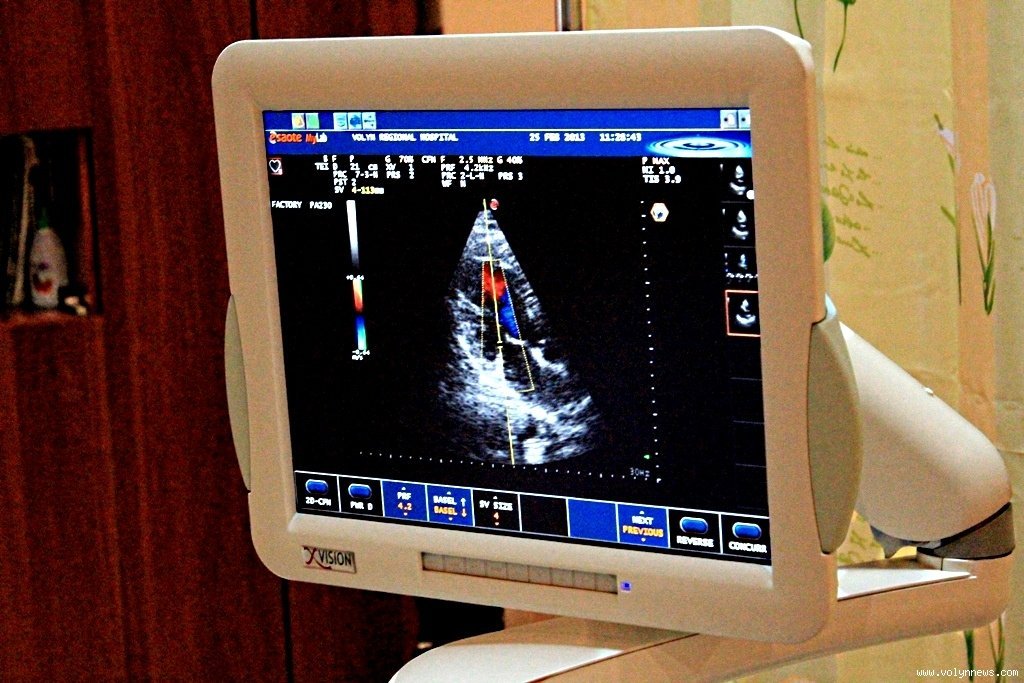

УЗД серця

Одним з головних етапів під час встановлення діагнозу є УЗД серця (ехокардіоскопія за допомогою ультразвукового сканеру серця).

«За результатами одного обстеження діагноз не ставиться. Робиться лише заключення. Тобто, описується структура серця: стан м`язу, клапани, аорти серця. Перевіряється, наскільки м`яз та клапани функціонально здатні. Потім на основі цього обстеження та електрокардіограми лікар-кардіолог виставляє клінічний діагноз», - ділиться досвідом лікар кабінету ехокардіоскопії Микола Литвин.